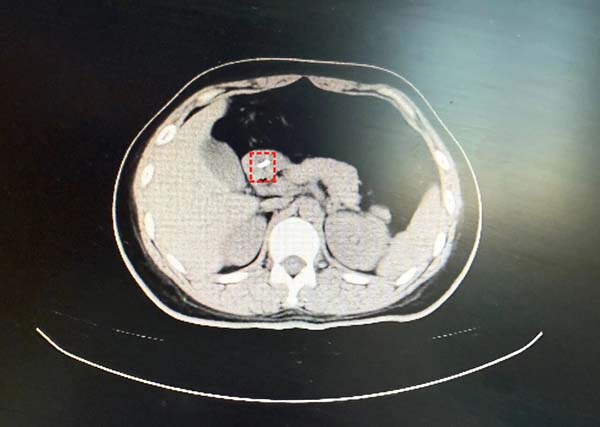

患者付某,女性,27岁,因“不慎吞食异物40分钟”于2025年12月23日18:04至中国中医科学院望京医院急诊外科就诊。患者无明显胸痛、腹痛、咽痛等不适。上腹、下腹、盆腔CT平扫:胃窦腔内细条形金属样高密度影,结合病史,考虑异物可能性大。与患者及家属充分沟通病情、交代内镜操作相关风险并获知情同意后,消化科牛然副主任医师带领内镜团队迅速为患者施行内镜下消化道异物取出术。镜下所见:进镜至十二指肠水平段时,于肠腔内探及一枚长约2厘米的金属细钉。该异物位置较深、形态细长,有坎顿、出血或穿孔的风险。幸运的是异物钳配合透明帽取出,过程顺利,所经过消化道粘膜观察无破损及划伤,患者无不适症状。

十二指肠水平部发现异物

异物钳配合透明帽取出过程